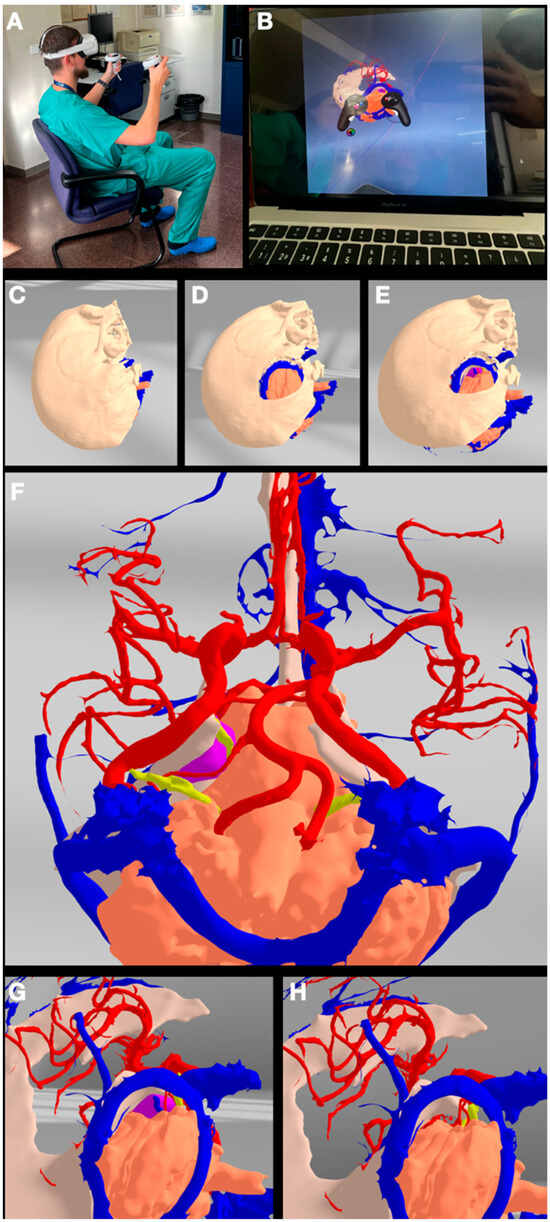

3.4. Case 4: Foramen Magnum Meningioma

| Step 6 | Import the reconstructed structures to Gravity Sketch on a Meta Oculus Quest 2 VR headset | Print the reconstructed structures |

| Assemble all the desired structures into the VR model | Assemble all the printed structures into the model | |

| Step 7 | The surgical case can be studied, analyzed, and detailed in VR | The surgical case can be performed, trained, and studied hands-on on the printed model |